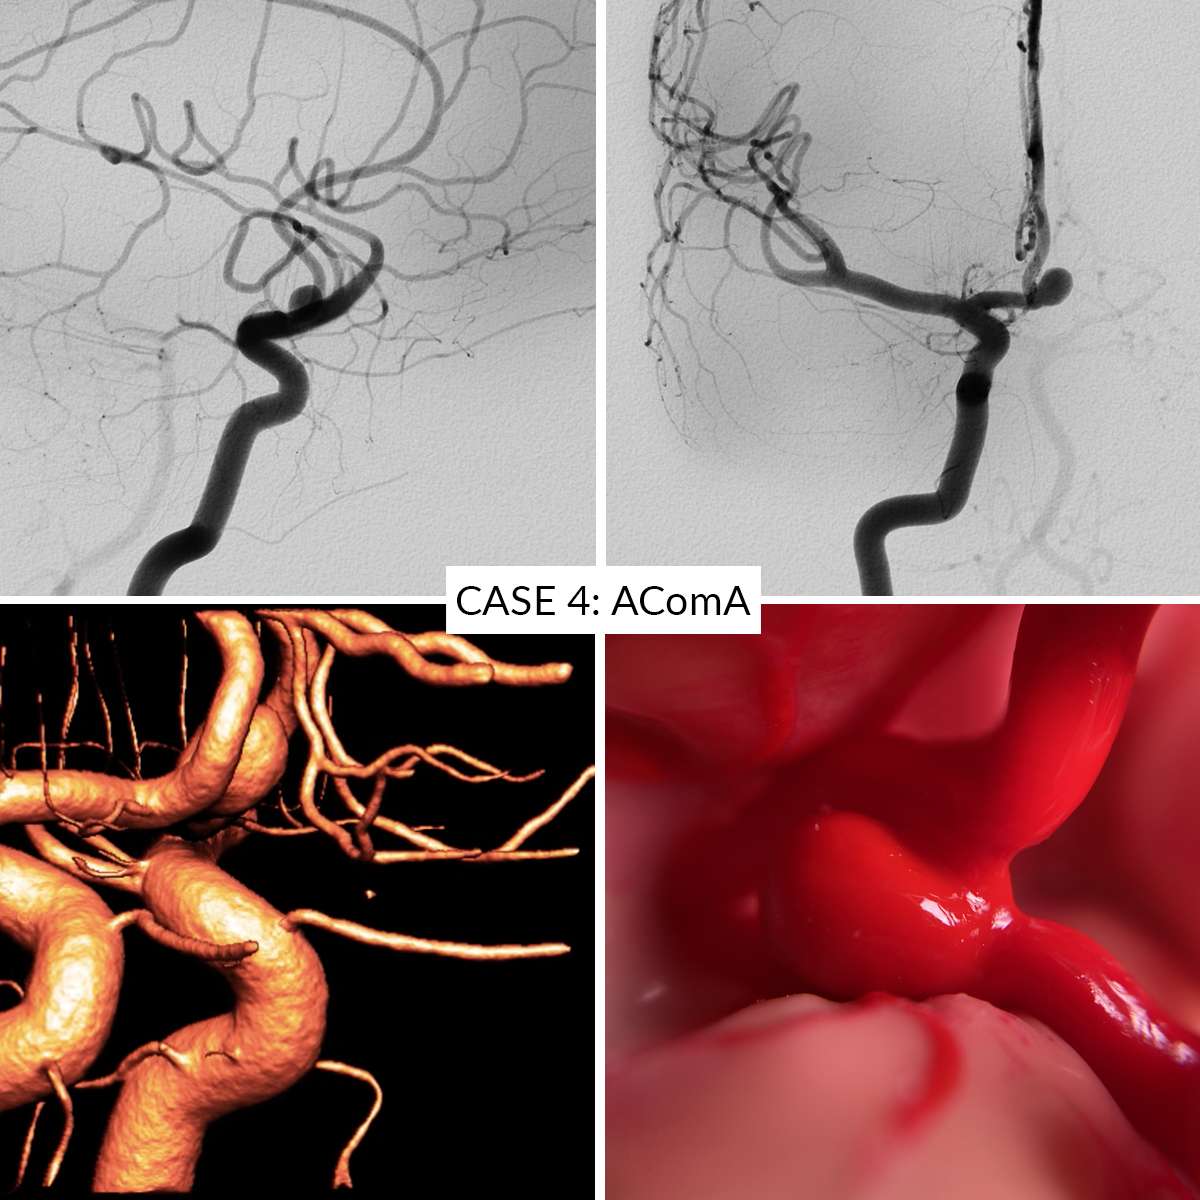

Case 4 : Anterior Communicating Artery

- Case 4: Anterior Communicating Artery